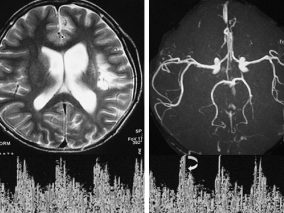

1小时条评论女,14岁,右利手。 主诉:突发右侧肢体偏瘫1年。 病史:1年前因突发右侧肢体活动障碍被外院诊断为脑梗死,在发病前没有外伤史、感染史(发热、上呼吸道感染、肠道感染),发病时无明显头痛。经保守治疗,保留右侧偏瘫后遗症至今。此后辗转于全国各大医院诊治查找...